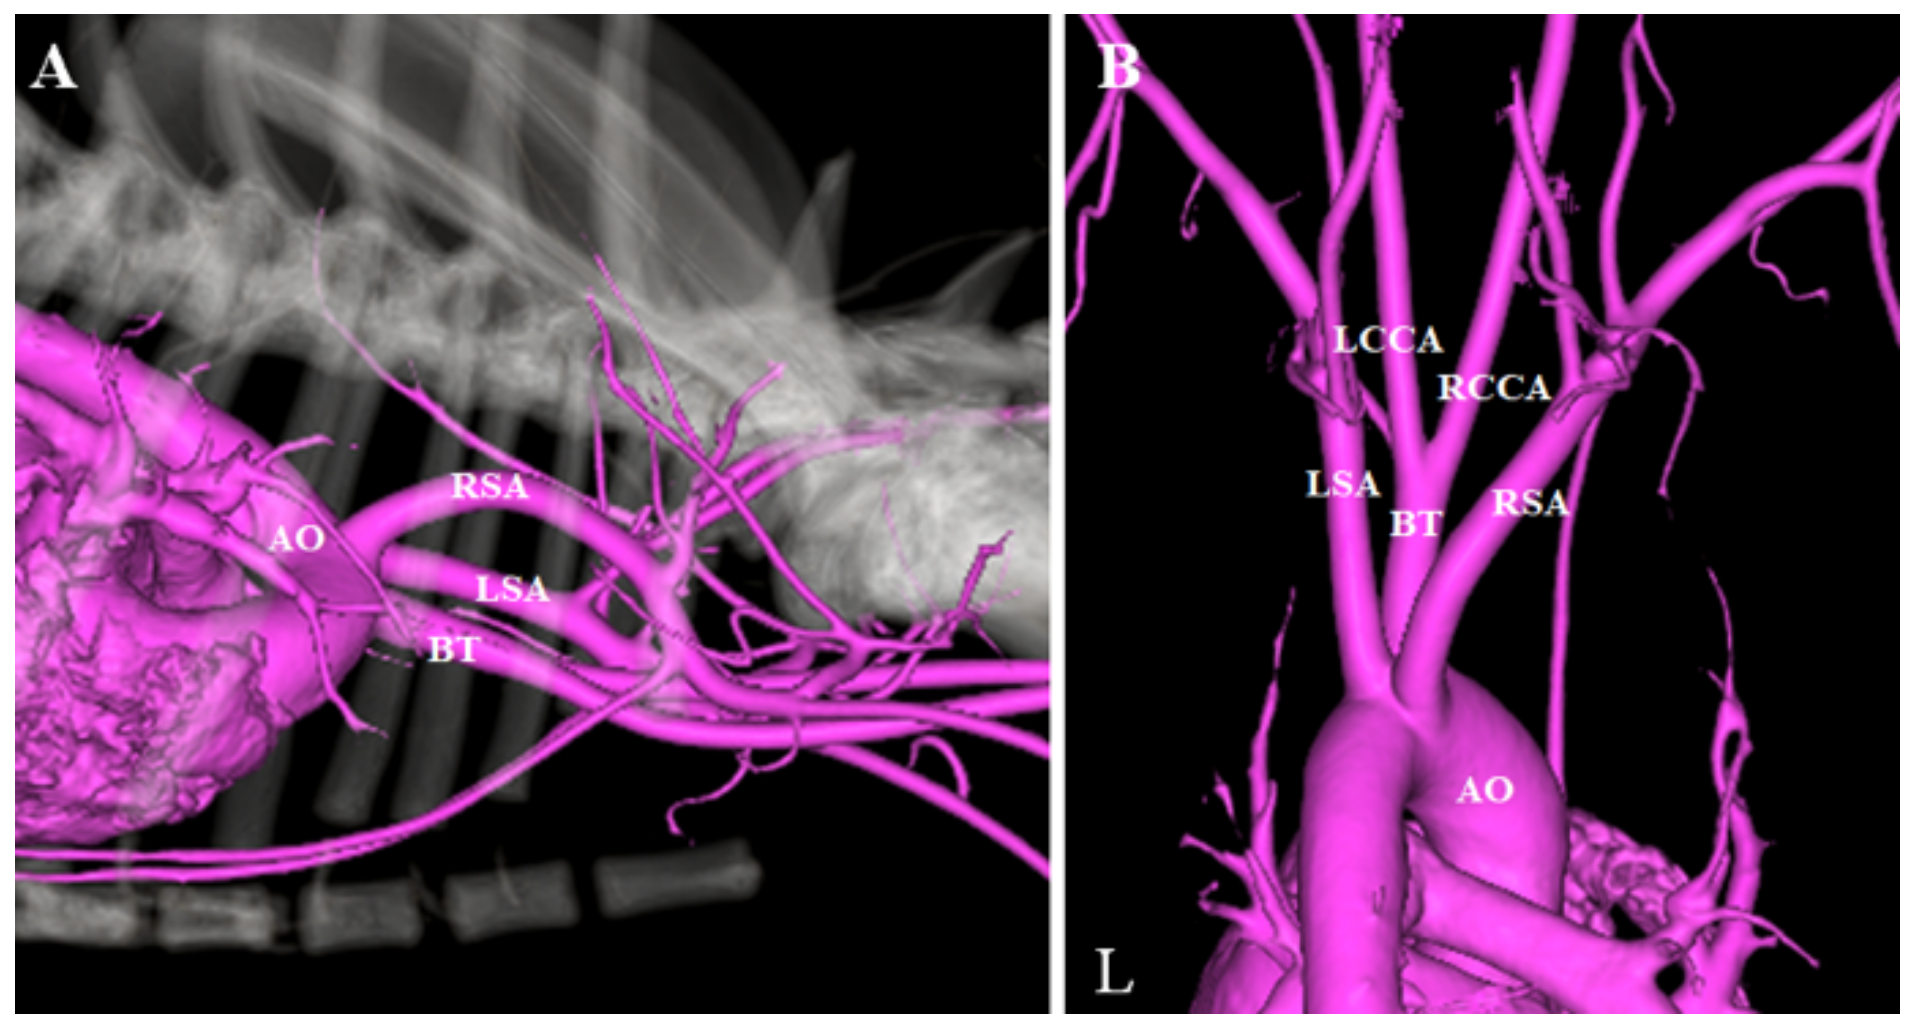

2. Case Presentation